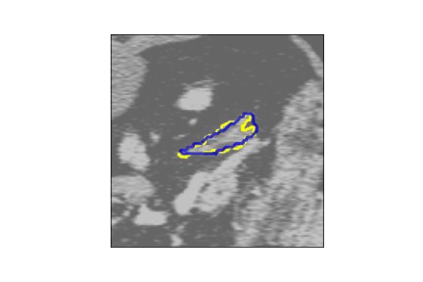

The human annotations are imperfect, especially when produced by junior practitioners. Multi-expert consensus is usually regarded as golden standard, while this annotation protocol is too expensive to implement in many real-world projects. In this study, we propose a method to refine human annotation, named Neural Annotation Refinement (NeAR). It is based on a learnable implicit function, which decodes a latent vector into represented shape. By integrating the appearance as an input of implicit functions, the appearance-aware NeAR fixes the annotation artefacts. Our method is demonstrated on the application of adrenal gland analysis. We first show that the NeAR can repair distorted golden standards on a public adrenal gland segmentation dataset. Besides, we develop a new Adrenal gLand ANalysis (ALAN) dataset with the proposed NeAR, where each case consists of a 3D shape of adrenal gland and its diagnosis label (normal vs. abnormal) assigned by experts. We show that models trained on the shapes repaired by the NeAR can diagnose adrenal glands better than the original ones. The ALAN dataset will be open-source, with 1,594 shapes for adrenal gland diagnosis, which serves as a new benchmark for medical shape analysis. Code and dataset are available at https://github.com/M3DV/NeAR.